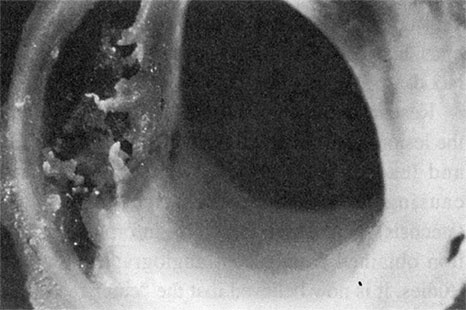

Иллюстрация к книге — Здоровое сердце. Издание XXI века [i_011.jpg]

Рисунок 1.7б. Нестабильная бляшка, отделенная от внутреннего просвета сосуда лишь тонким слоем клеток, имеет большую вероятность разрыва. Снимок предоставлен доктором Майклом Дж. Дэвисом